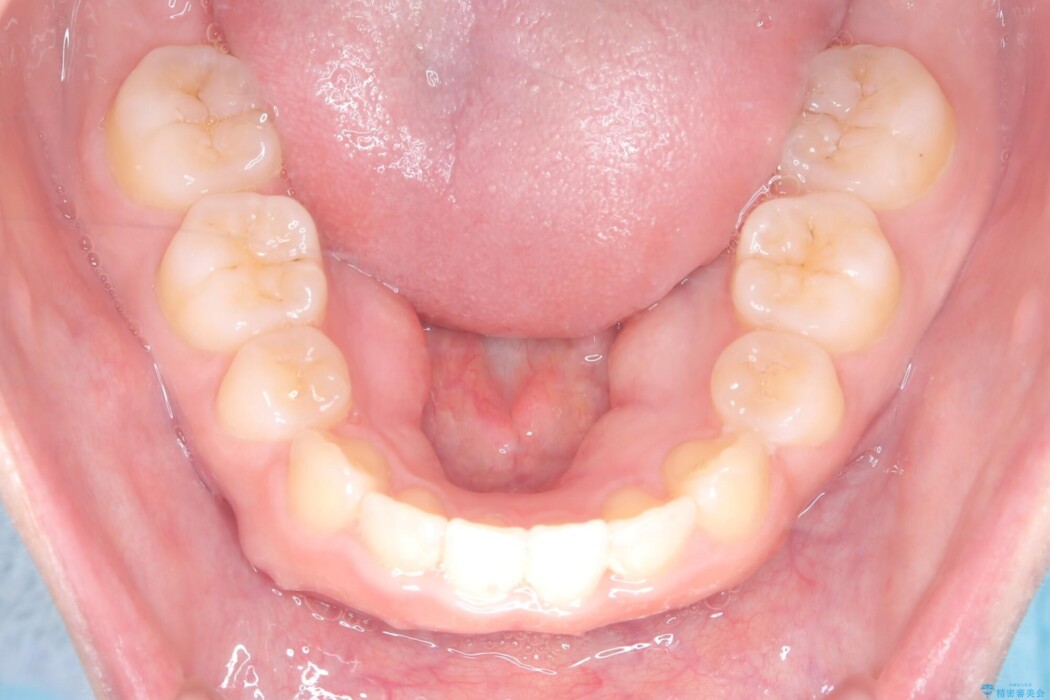

治療概要

- 患者様:20代女性

- 治療期間:2年6ヶ月

- 治療回数:30回以上

- 矯正装置:ワイヤー(審美装置)

- 概算治療費:100万円

※費用は治療当時の料金となります - 担当医:河口智英

治療動機

口元の突出感が気になるとご来院された患者様です。

治療計画

矯正検査の結果、前歯が外側に強く倒れ込んでいる「唇側傾斜(しんそくけいしゃ)」が認められ、口元の突出感の原因になっていました。

この傾斜を根本から正し、前歯を十分に後方へ下げるスペースを確保するため、上下左右の4番を抜歯し、目立ちにくい審美ワイヤー装置にて治療を行うこととしました。